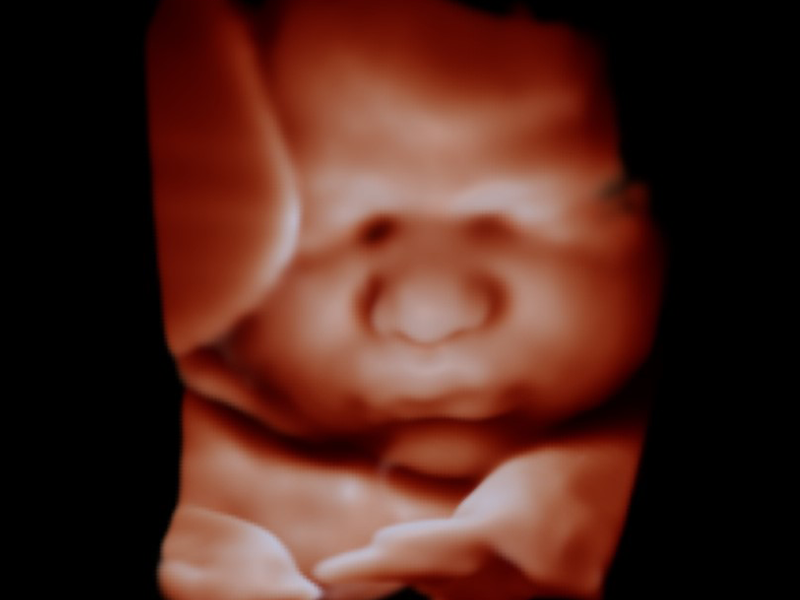

- A brief glimpse of your baby in 3D